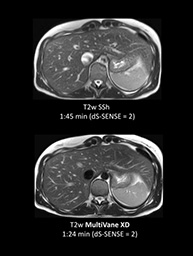

Ingeniaリリース5は,新しいユーザーインターフェイスとアプリケーションが搭載されました。リリース5は日々のワークフローの改善と新たな臨床応用への挑戦を可能にします。新たに搭載されたユーザーインターフェイスは,従来に比べ日々の条件設定を簡便化させ,施設毎のニーズに合った撮像条件を設定することができます。また,新しい定量化アプリケーションとして,頭部Perfusion評価(pCASL)や,T2・T2*の撮像法として肝臓の脂肪沈着(mDIXON Qaunt),心筋の評価(Star Qaunt),膝の骨軟部評価として新たな撮像法が加わり臨床応用への展開が期待できます。更に,動き補正法が新しくなりMultiVane XDとしてシーケンスデザインが一新され,SENSE倍速の併用が可能になりスキャン時間の短縮と画質向上を実現しました。MRコーナーではこれらアプリケーションを分かりやすく解説し,デモコンソールで改善されたワークフローを体験頂きたいと思っております。

動き補正 MultiVane XD |